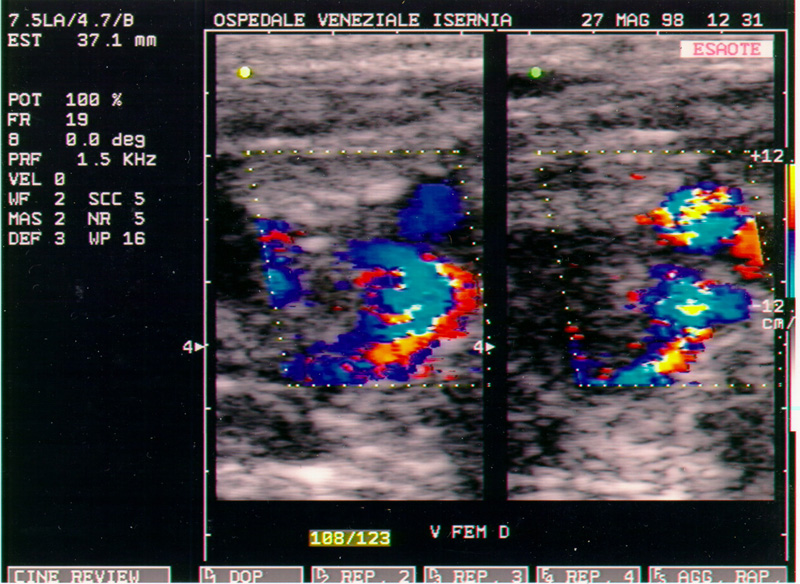

Nel maggio del 98 Maddalena viene ricoverata all'Ospedale di Isernia, per un sospetto virus allo stomaco, la terapia non dà alcun risultato. L'8 luglio viene urgentemente ricoverata all'Ospedale di Agnone. Si scopre un carcinoma invasivo al pancreas. E' colta dalla signora MORTE il 30 agosto 1998 alle cinque ed un quarto del mattino. Il calendario festeggia Santa Tecla. Due giorni dopo invece, se fosse stata in vita, sarebbe ricorso il 47esimo anno di matrimonio. E' morta alla stessa ora in cui era nata. Alle cinque del mattino.